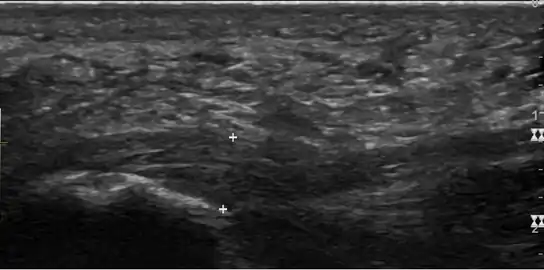

Thickened plantar fascia in ultrasound

The plantar fascia has three fascicles-the central fascicle being the thickest at 4 mm, the lateral fascicle at 2 mm, and the medial less than a millimeter thick.[18] In theory, plantar fasciitis becomes more likely as the plantar fascia's thickness at the calcaneal insertion increases. A thickness of more than 4.5 mm ultrasound and 4 mm on MRI are useful for diagnosis.[19] Other imaging findings, such as thickening of the plantar aponeurosis, are nonspecific and have limited usefulness in diagnosing plantar fasciitis.[13]